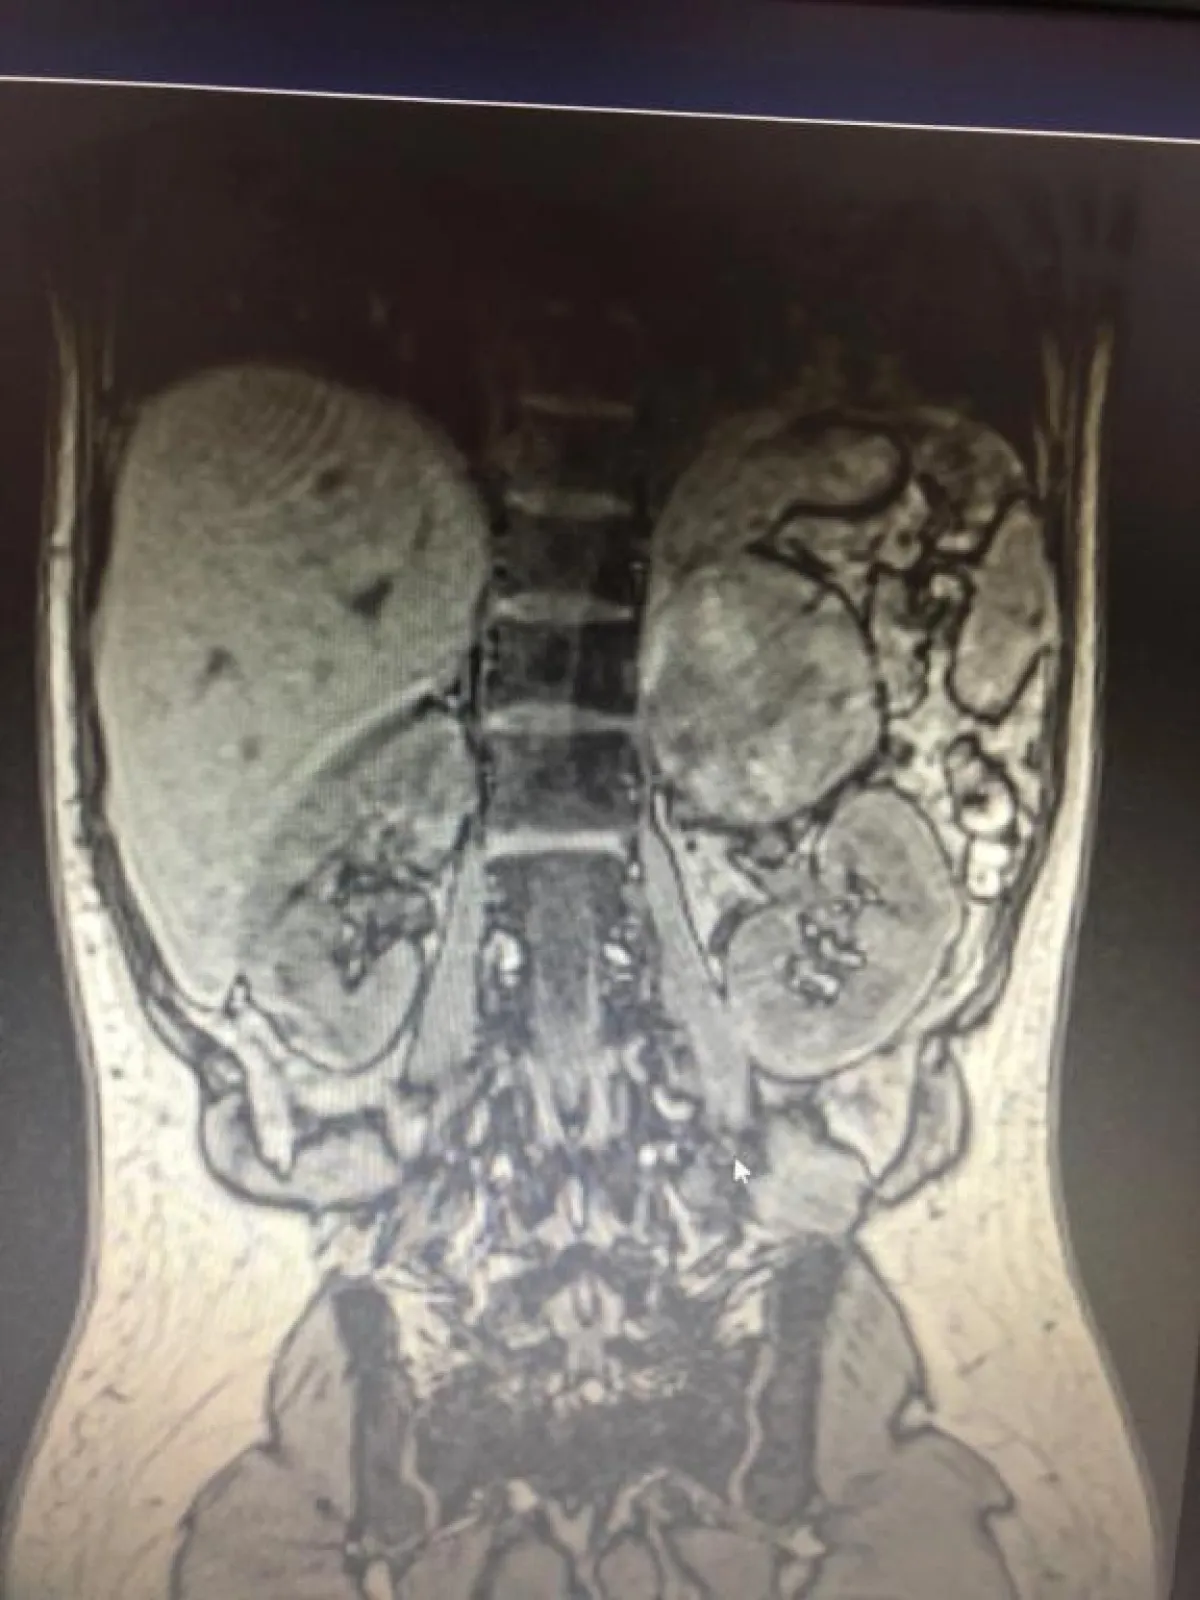

وعلى الفور تم تحويل المريضة للعناية المركزة وبعد إجراء الفحوصات اللازمة والأشعة المغناطيسية والتحاليل الهرمونية اكتشف أن المريضة تعاني من فرط إفراز الغدة الكظرية (فيوكروموسيتوما).

وأوضح الدكتور عوض القحطاني استشاري الغدد الصماء وقائد الفريق المعالج أن هذه من الحالات النادرة والخطيرة لأن ارتفاع ضغط الدم أو انخفاضه الشديد يؤدي إلى الوفاة بشكل مباشر، كما أن الموقع التشريحي للغدة الكظرية فوق الكلى يجعل عملية استئصالها بالمنظار صعبة ويتطلب كفاءة عالية من جراح المناظير والتخدير حتى يتمكن من إحكام السيطرة على الضغط الدموي أثناء وبعد التخدير والتدخل الجراحي.